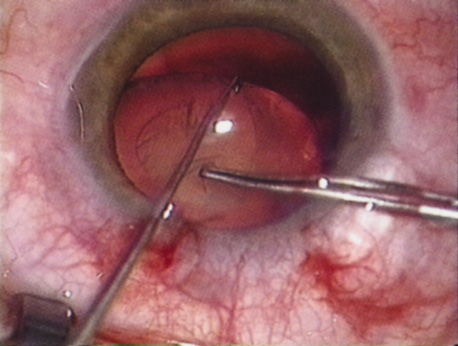

The introduction of innovative adjunctive devices was able to improve the management of challenging cases. The capsular tension ring introduced independently by Tsutomu Hara37 and Toshiyuki Nagamoto38 in Japan was identified as a major weapon in managing zonular weakness by Ulrich Legler and Bernd Witschel of Germany.39 The CTR came to the United States in 1993,40 after which modifications by Robert Cionni,41 Iqbalk Ahmed and Alan Crandall,42 and Burkhard Dick were developed. Iris reconstruction had been primarily limited to suture techniques developed by Malcolm McCannel43 and later Steven Siepser.44 The prosthetic irides were introduced by German surgeons, Ranier Sundmacher45 and Volker Rasch,46 and brought to the United States by Kenneth Rosenthal and then Robert Osher in 1996.47 Although many devices had been developed to mechanically open the small pupil, it was the stretch technique developed by Luther Fry that greatly simplified these difficult cases.48 Improving visibility by staining the anterior capsule of the white cataract was introduced by Masayuki Horiguchi from Japan (ICG)49 and Gerritt RJ Melles from The Netherlands (Trypan Blue).50